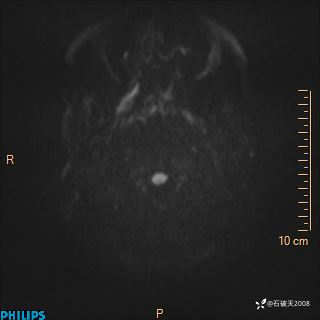

ADC